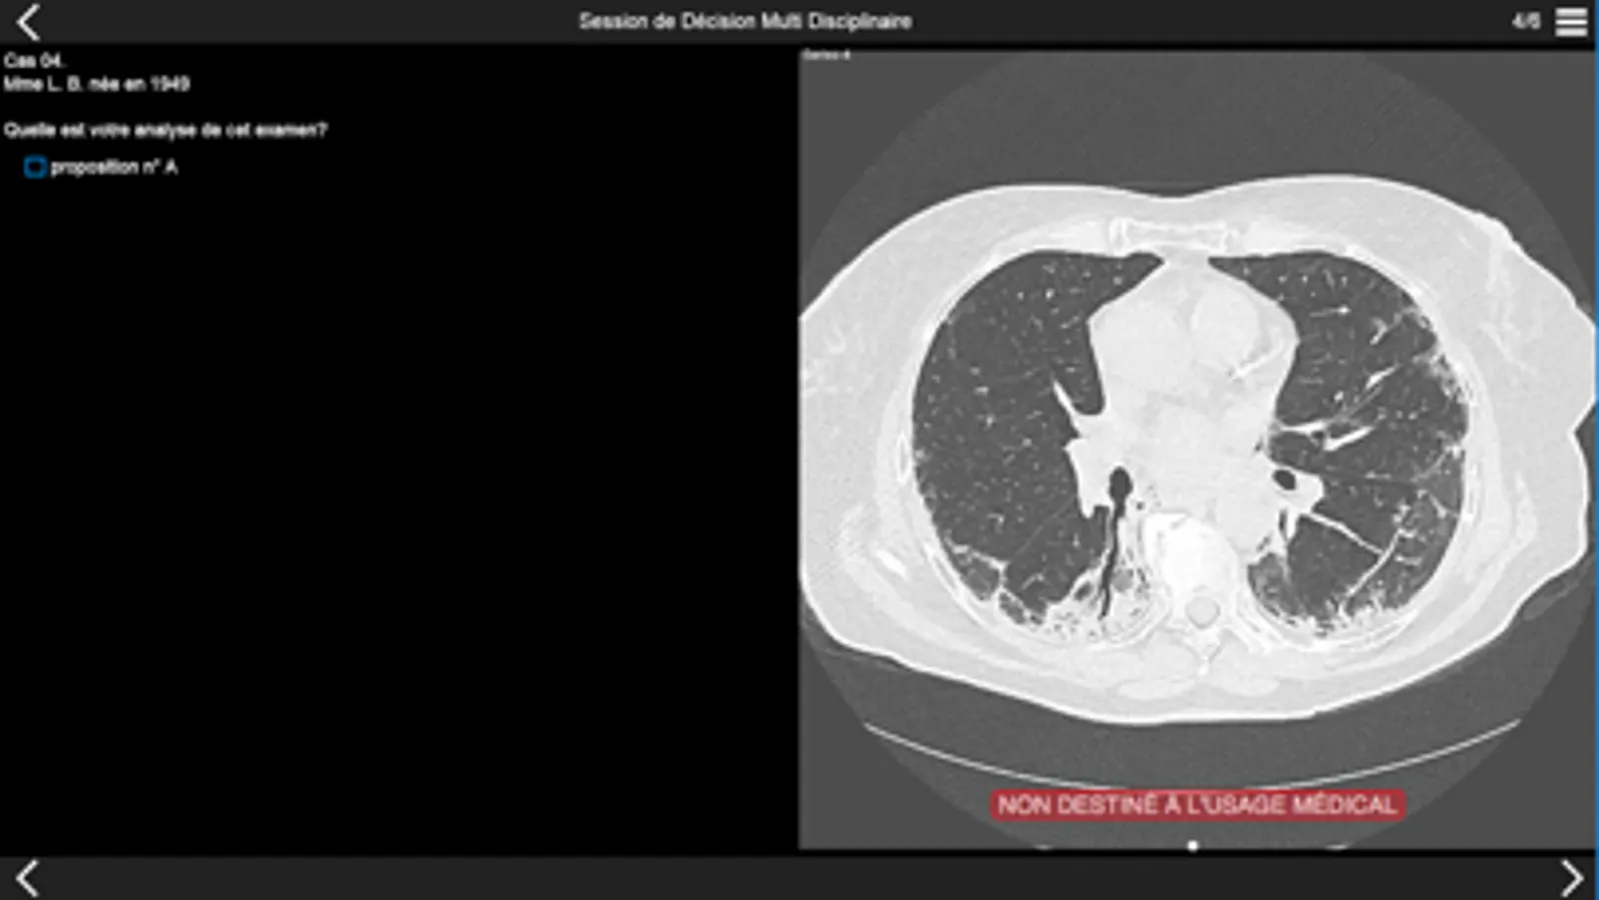

Consultez les examens tomodensitométriques des cas cliniques de pneumopathie infiltrante présentés lors de la session de discussion multidisciplinaire qui aura lieu dans la première partie de l'après-midi.